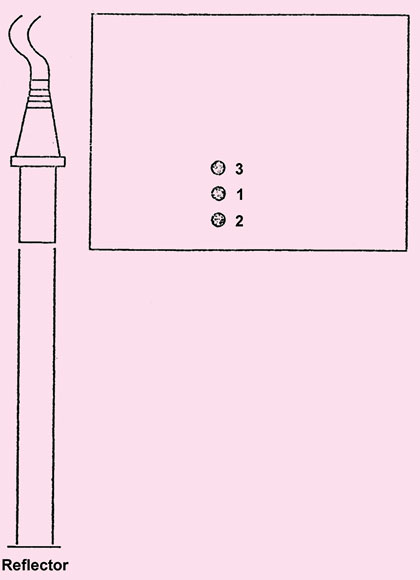

- A mode: A mode (amplitude mode) is the most basic form of diagnostic ultrasound, here a single beam of ultrasound is analyzed, hence in this mode the ehoes are shown as peaks and the distance between the various structures and transducer can be measured (Fig. 1.12) and is displayed on time axis. Time and distance are interchangeable because an echo is assumed to travel at a constant speed in the body tissue (1540 m/sec), time it takes for the echo to return to the transducer can be converted to the distance. This mode is now almost obsolete (Fig. 1.12).